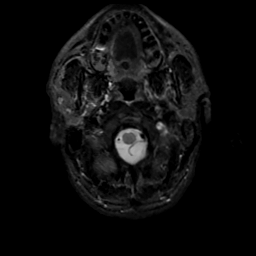

MR Study #13, May 19, 1991 -- Slice #2

[Home][Help][Clinical][Tour 1][Tour 2] Slice 2